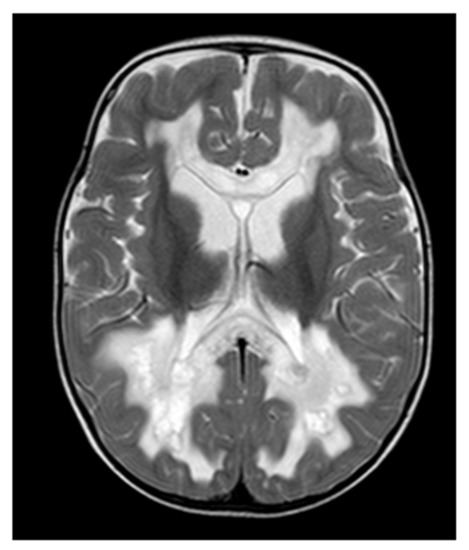

HPDL encodes 4-hydroxyphenylpyruvate dioxygenase-like protein, whose function is not fully understood by now [59]. Recent studies indicate that 4-hydroxymandelate (4-HMA), an intermediate involved in CoQ10 biosynthesis, is a product of HPDL [6]. In 2020, Husain et al. described clinical and brain MRI findings in 17 individuals with bi-allelic HPDL variants (OMIM #619026) [60]. Clinical features in these patients reached from developmental delay, seizures and microcephaly to non-neurological manifestations. Based on the MRI images, the authors described different patterns of brain lesions. Abnormalities included symmetrical T2-hyperintensities of basal ganglia and brain stem, white matter abnormalities and cortical lesions. In one individual, there was suspicion of a transient spinal pathology. Three out of four individuals showed a lactate peak on MR spectroscopy.

In 2021, Wiessner et al. reported 34 individuals with HPDL deficiency. Phenotypically, all individuals described showed spasticity (OMIM #619027) [61]. Some of the individuals presented with ataxia or oculomotor abnormalities. The most severely affected patients showed global developmental delay, seizures and encephalopathy. Depending on the severity of the clinical phenotype, patients were divided into three groups. Individuals showing the mild phenotype displayed no abnormalities on brain MRI. Patients with intermediate and severe phenotypes presented with corpus callosum abnormalities. Cerebellar atrophy and bilateral inferior olivary hyperintensities on T2-weighted MRI images were shown for the intermediate phenotype. One individual with a severe phenotype presented with an MRI consistent with Leigh syndrome, and MR spectroscopy showed a lactate peak [62].

In addition to the reported individuals, we recently identified an infant with HPDL deficiency (not yet published). The girl presented with seizures, global developmental delay and microcephaly at the age of 3 months. The brain MRI showed subcortical T2-hyperintense lesions predominantly in the right frontal region (see Figure 6). Moreover, bilateral thalamic lesions were seen. MR spectroscopy did not reveal clear abnormalities.

Figure 6.

Neuroimaging in HPDL deficiency: (A) Brain MRI, T2-weighted images of a 3-month-old girl with HPDL deficiency. Images show subcortical T2-hyperintensities, mainly affecting the right frontotemporal regions. Moreover, asymmetrical signal abnormalities of the thalami are visible (white arrows). (B) No cerebellar abnormalities are visible.